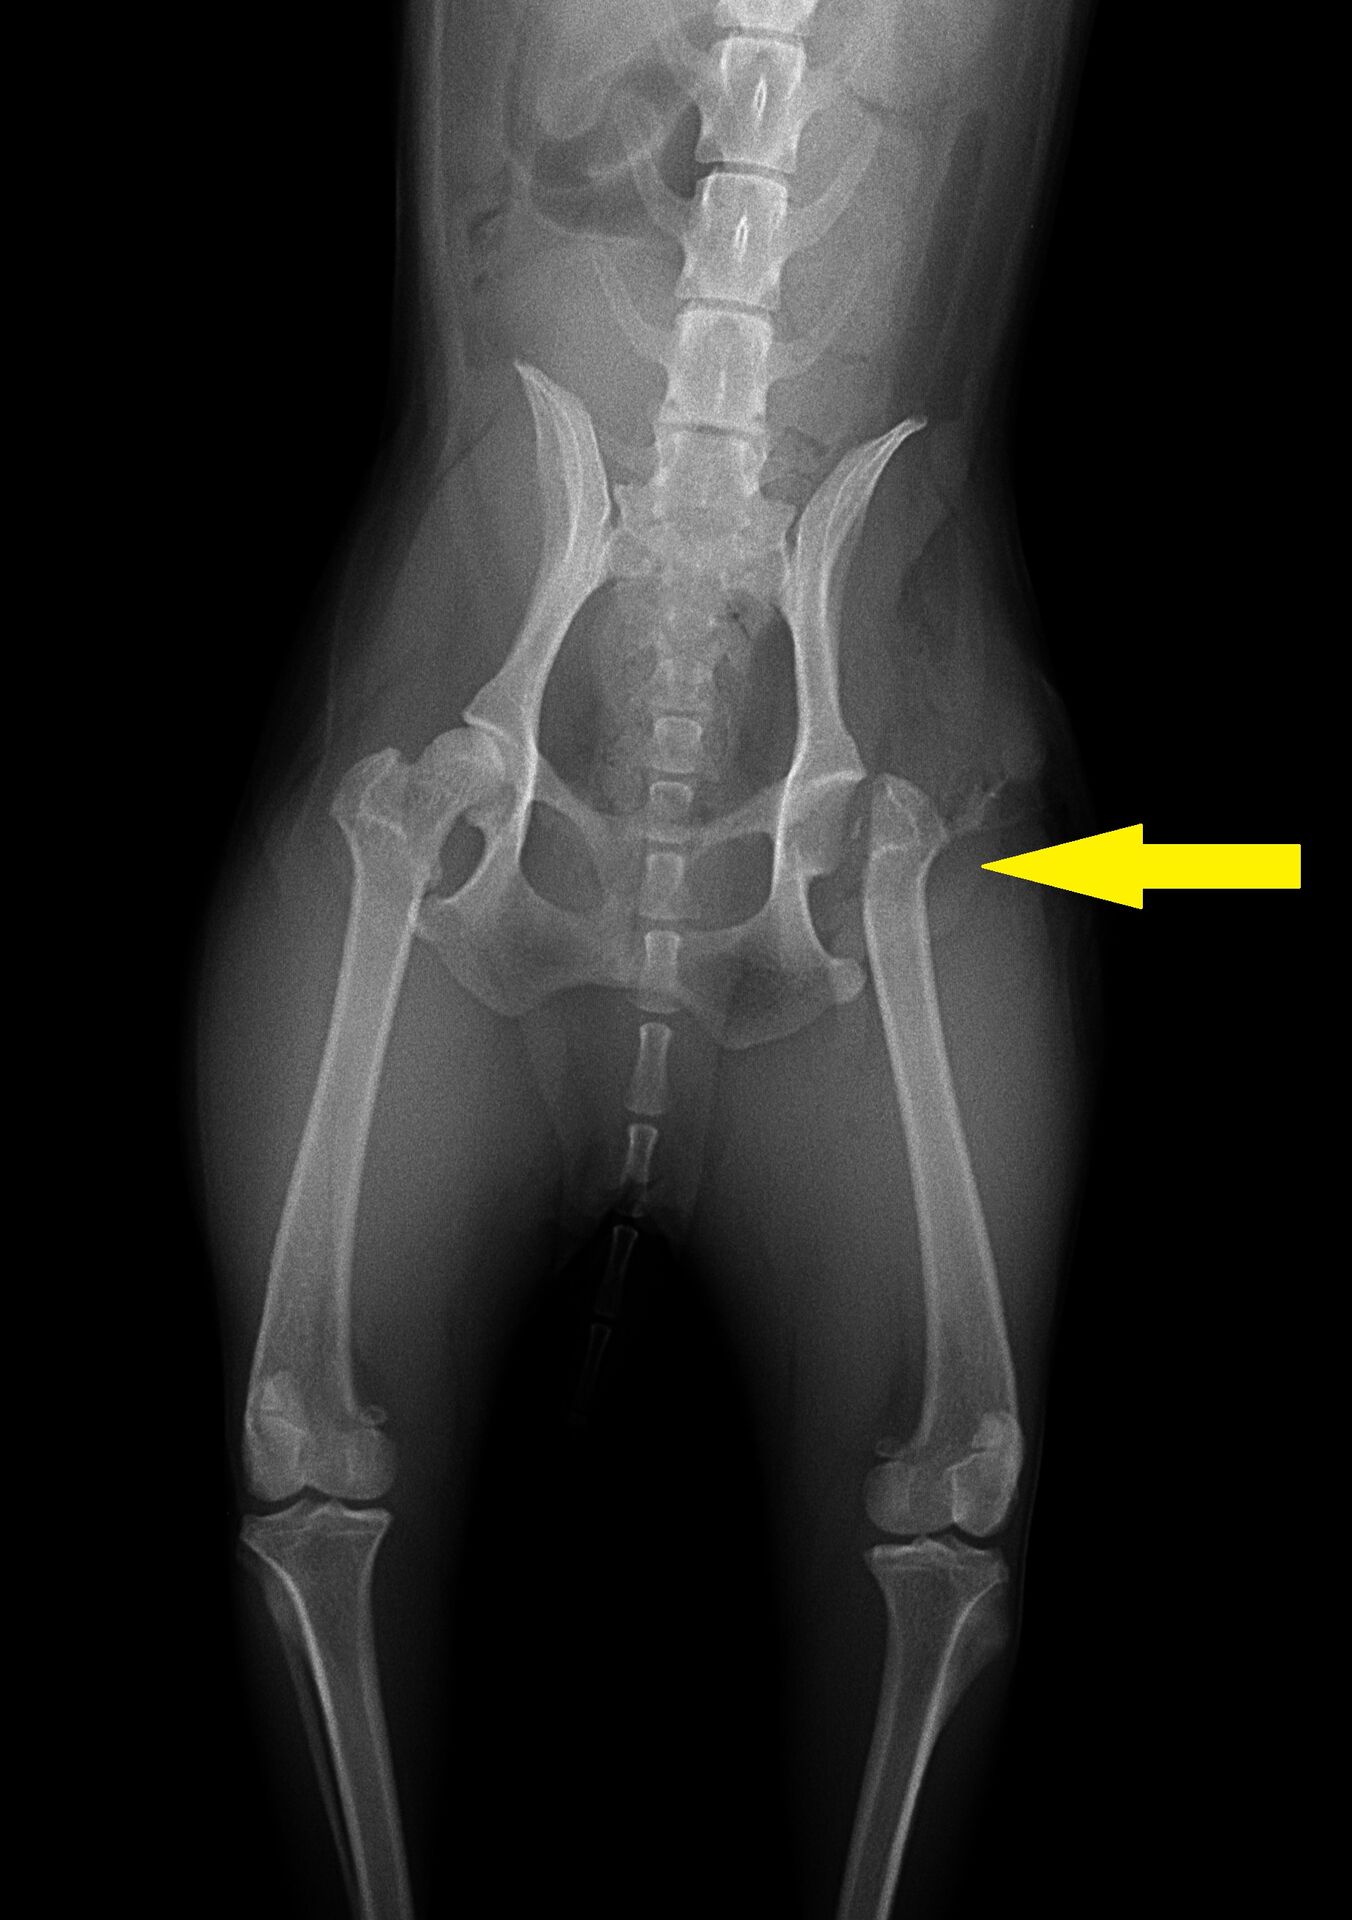

今回のワンちゃんは階段から落ちた時に外れたようです。外れた直後のレントゲン写真が下です。

かなり痛がっていたので、体勢が整って撮影できていません。